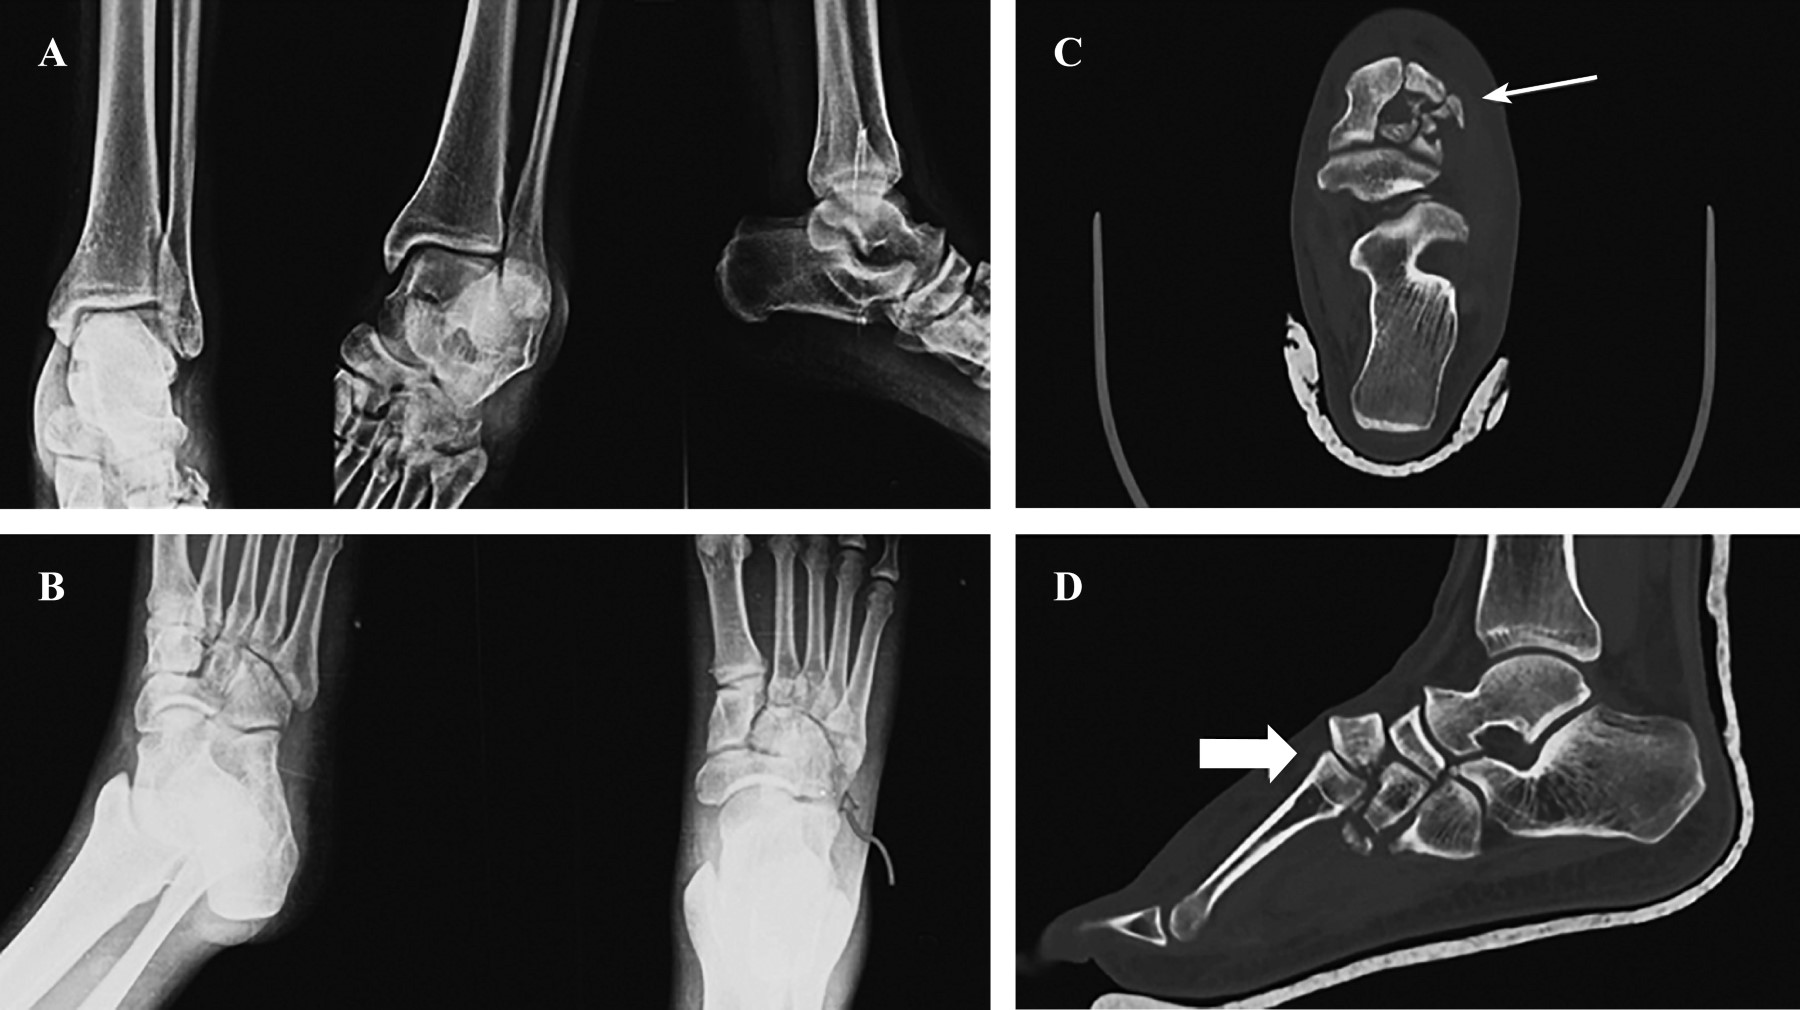

Figure 1